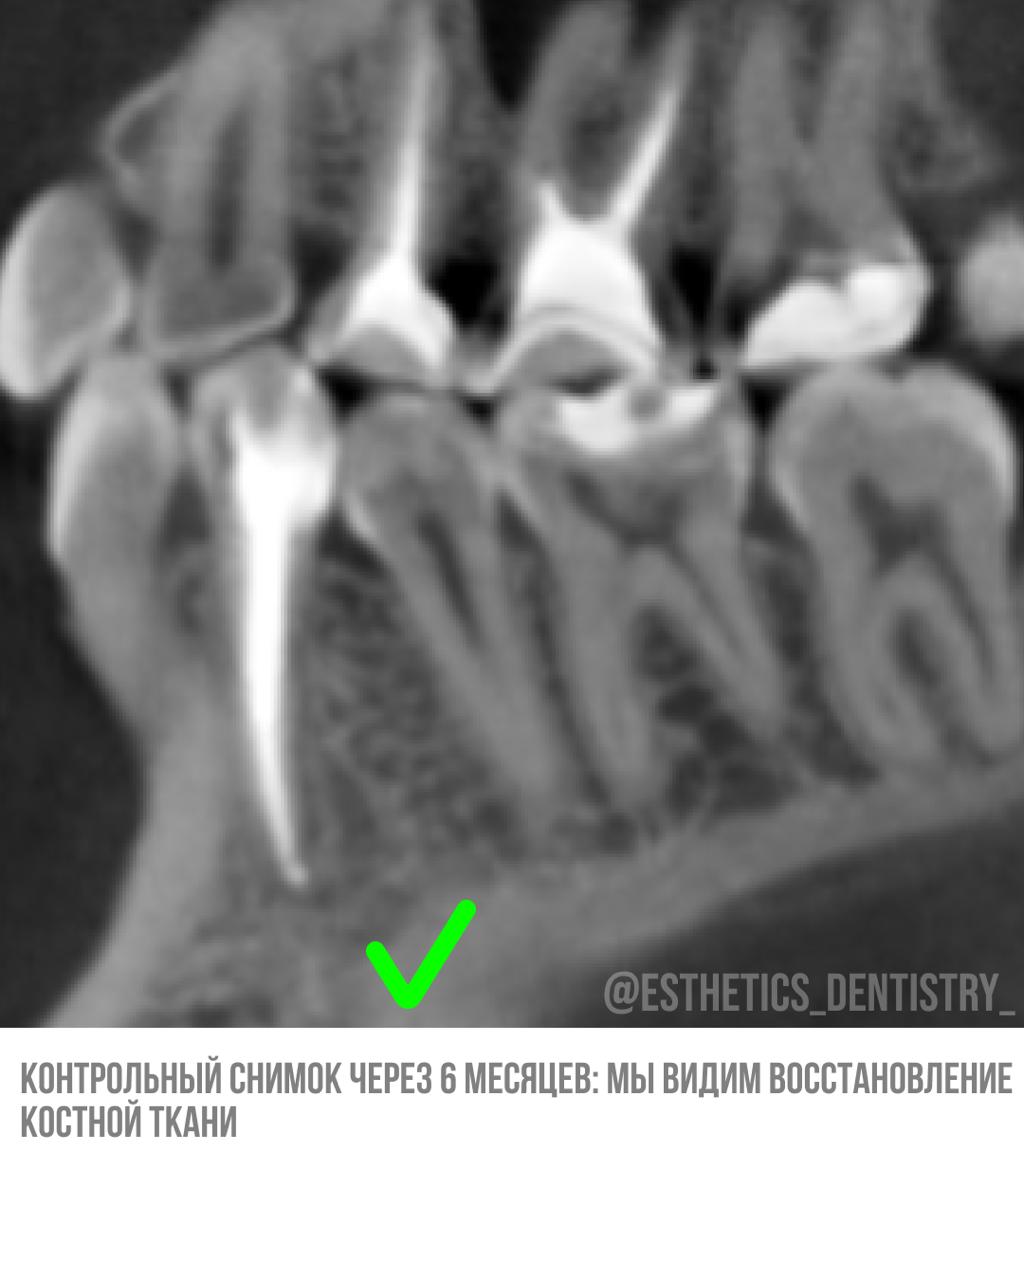

Кейс лечение кисты

Терапия